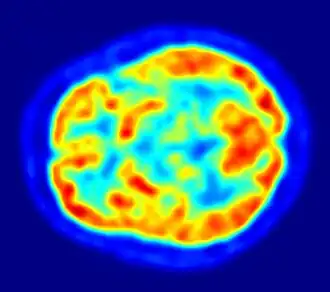

Hay varios métodos para detectar los cambios de actividad cerebral mediante imágenes tridimensionales de los cambios locales en el flujo sanguíneo cerebral. Los antiguos métodos son la SPECT y la PET, que dependen de la inyección de marcadores radiactivos en el torrente sanguíneo.

La imagen por resonancia magnética funcional (IRMf), tiene considerablemente mejor resolución espacial y no implica ninguna radiactividad.[25] La IRMf puede localizar los cambios de actividad cerebral en regiones tan pequeñas como 1 mm³ (milímetro cúbico).

El inconveniente es que la resolución temporal es pobre: cuando aumenta la actividad cerebral, el flujo sanguíneo responde con un retraso de 1 a 5 s (segundos) y tiene una duración de al menos 10 s. Por lo tanto, la IRMf es una herramienta muy útil para saber cuales regiones del cerebro están involucradas en una determinada conducta, pero da poca información sobre la dinámica temporal de sus respuestas. Una ventaja importante de la IRMf es que, debido a que no es invasiva, puede ser fácilmente utilizada en seres humanos.

Aunque el cerebro humano representa tan solo el 2 % del peso corporal, recibe el 15 % del gasto cardíaco y el 20 % del consumo total de oxígeno del cuerpo, y usa el 25 % de la glucosa total del cuerpo.[31] La necesidad de limitar el peso corporal con el fin, por ejemplo, de volar, ha llevado a la reducción del tamaño del cerebro en algunas especies, como los murciélagos.[32] El consumo de energía del cerebro no varía en demasía con el tiempo, pero las regiones activas de la corteza consumen más energía que las regiones inactivas: este hecho forma la base de los métodos de imagen cerebral funcional por PET y fMRI.[33] Estos son técnicas de imagen de medicina nuclear que producen una imagen tridimensional de la actividad metabólica.